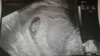

To i ja się pochwale :) 8t4d ciąża starsza niż OM termin 27.11 :) kruszyna ma 1.86cm [emoji7]

...........:::::::6tydz i 2dni:::::::::..........